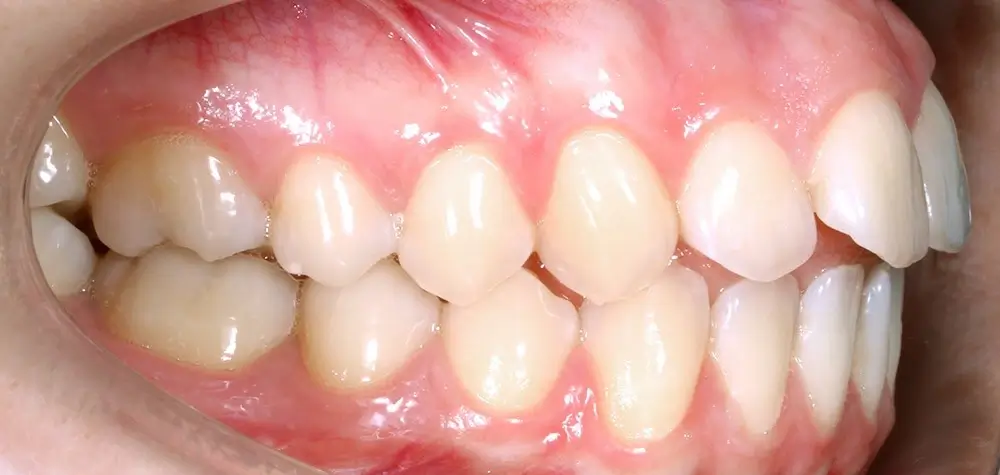

Открытый прикус - Кейс 6

Эффективность устранения дефекта прикуса посредством элайнеров FlexiLigner.

Результаты лечения